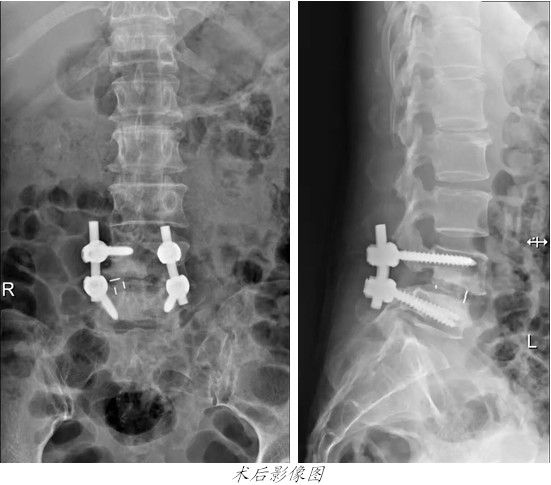

康美醫院開展微創手術治療腰椎滑脫2016-10-25

昨天,康美醫院爲一名腰椎滑脫患者成功進行了脊柱微創手術。

患者歐**,女,48歲,兩個多月前無明顯誘因出現腰部疼痛伴右大腿酸痛,予以康複理療及口服藥物治療,症狀稍減輕,但反複出現。來我院行腰椎MRI檢查,結果顯示第四腰椎向前滑脫,雙側椎弓峽不連,随入住我院外四科(骨科)。

經外四科主任吳志斌詳細檢查,認爲患者第四腰椎真性滑脫,Meyerding分級爲Ⅱ度,腰4/5椎間隙消失,神經壓迫症狀明顯,一般治療難以改善患者日常生活質量,有手術治療指征。經與患者溝通一緻,昨天[ 查看詳細 ]